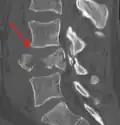

A burst fracture of L4 as seen on plane X ray -

A burst fracture of L4 as seen on CT -